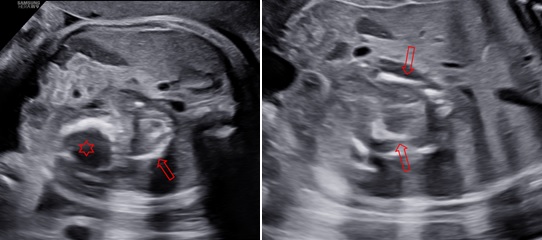

Siêu âm ngã bụng với máy HERA W9 (Samsung) ở các thời điểm 31 tuần 4 ngày, 34 tuần 3 ngày và 39 tuần. Ở hạ sườn trái và cực trên của thận trái có một khối không đồng nhất với kích thước tăng theo tuổi thai lần lượt là: 45x50x42mm, 48x58x50mm và 80x74x66mm. Bên trong khối này thấy hình ảnh vôi hoá có dạng của xương vòm sọ, xương đùi, xương sống và hình ảnh các cấu trúc này rõ khi tuổi thai lớn hơn. Trên Doppler màu, có một mạch máu nuôi khối này xuất phát từ động mạch chủ bụng của thai vật chủ với dạng sóng của động mạch rốn.

Hình 2: Thai 34 tuần 2 ngày, mặt cắt ngang và dọc bụng cho thấy trong khối này có các cấu trúc giống vòm sọ (dấu sao) và cột sống và xương đùi (mũi tên)

Hình 3: Thai 39 tuần, mặt cắt ngang và dọc bụng, cho thấy trong khối này có các cấu trúc giống vòm sọ (dấu sao) và cột sống (mũi tên) được quan sát rõ hơn.

Hình 5: Siêu âm em bé sau sinh, ở sau phúc mạc và trên thận có một khối không đồng nhất với hình ảnh vòm sọ (dấu sao) và cột sống (mũi tên)